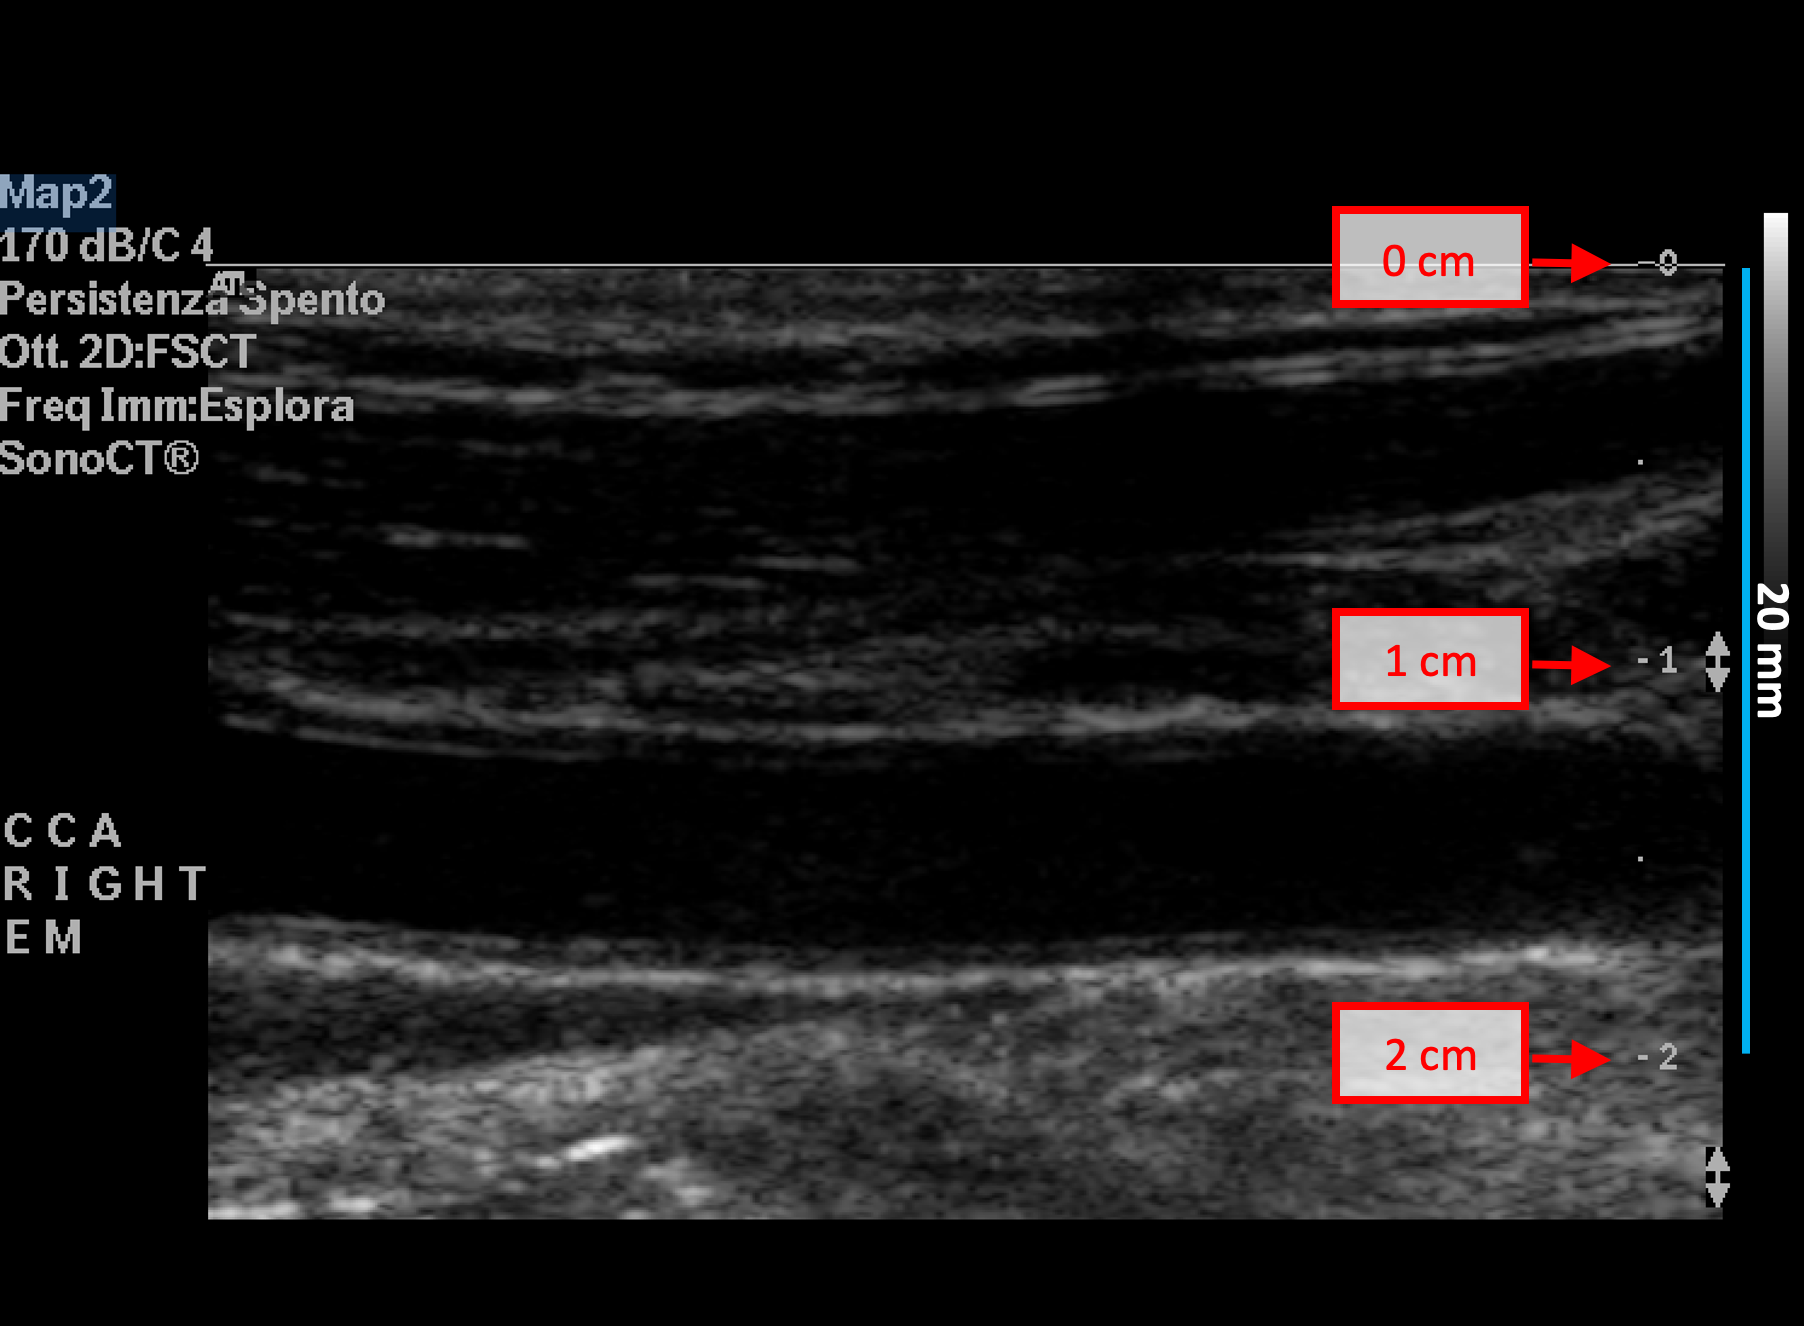

Exemples d'étalonnage en mode B

Les images suivantes présentent des exemples d'étalonnage de l'image en mode B. Les éléments graphiques en rouge indiquent où trouver les informations relatives à la profondeur de l'image échographique.